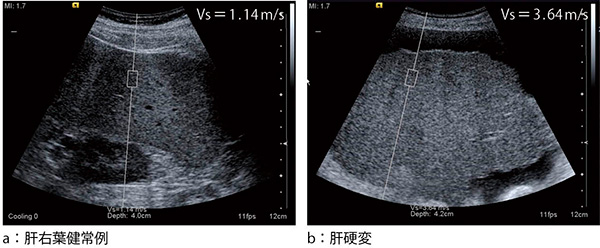

ARFIはまた,生体深部の組織を振動させて,剪断弾性波(shear wave)を発生させることができる。生体組織を弾性体と仮定すると,shear waveの伝搬速度は組織硬度に相関することが知られているので,発生させたshear waveが伝搬する速度(m/s)を測ることによって,従来実現が難しかった硬さの数値測定が可能になった(図2)。

図2 VTQによる肝硬度測定

(画像ご提供:東京医科大学放射線科・河本敦夫先生)